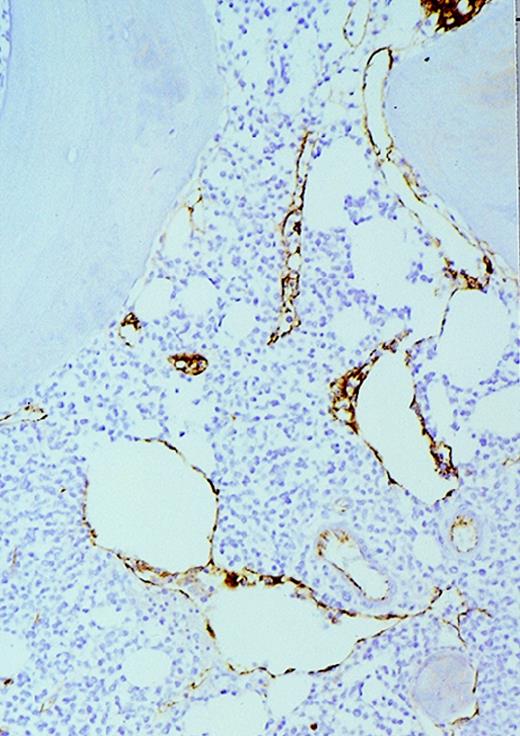

The patients with AML consisted of 8 women and 12 men; the control patients consisted of 12 women and 8 men. The mean age of the AML patients was 59 years (range, 24-87 years). In the control group, the mean age was 49 years (range, 27-71 years). The FAB distribution of the AML cases was as follows: 2 M0, 6 M1, 6 M2, 4 M4, and 2 M7. The cellularity (average ± SEM) was 78% ± 26% (range, 25% to 100%) and 49% ± 8% (range, 35% to 65%) for AML and normal marrows, respectively (P < .0001). Using ULEX-E staining, AML marrows had (average ± SEM) 8.3 ± 3.6 vessels/mm (range, 3.7-19.3) while normal marrows had 4.3 ± 1.8 vessels/mm (range, 1.6-7.9). Using vWF staining of the same specimens, AML marrows had 8.6 ± 3.0 vessels/mm (range, 3.7-15.8) and normal marrows had 4.9 ± 2.2 vessels/mm (range, 1.5-10.1). The differences between the numbers of vessels/mm in AML and normal marrows were highly significant (P < .0001 for both ULEX-E and vWF staining). ULEX-E and vWF exhibited similar staining patterns. Figures1 and 2 show examples of vascularity in normal and AML marrows.

Vascularity of normal and AML marrow specimens.

Normal or AML bone marrow samples were stained with H&E or for vWF expression (see Methods) for vessel scoring. Legends (all ×200): A = normal bone marrow with H&E stain; B = normal bone marrow with vWF stain; C = AML bone marrow with H&E stain; D = AML bone marrow with vWF stain. The normal bone marrow shows strong staining for vWF in megakaryocytes but no evidence of increased vessels. The AML marrow has significantly more vessels than the normal marrow. These sections are representative of the whole series.

High-power view of vascularity of normal and AML marrow specimens.

Normal or AML bone marrow samples were stained for vWF expression (see Methods). A = 600× view of normal bone marrow showing positive staining in a megakaryocyte as well as 1 vessel. B = 400× view of representative AML marrow showing numerous vessels. Note that some of the vessels are large with irregular and bizarre shapes. C = 600× view of representative AML marrow showing details of vascular endothelial cell staining.